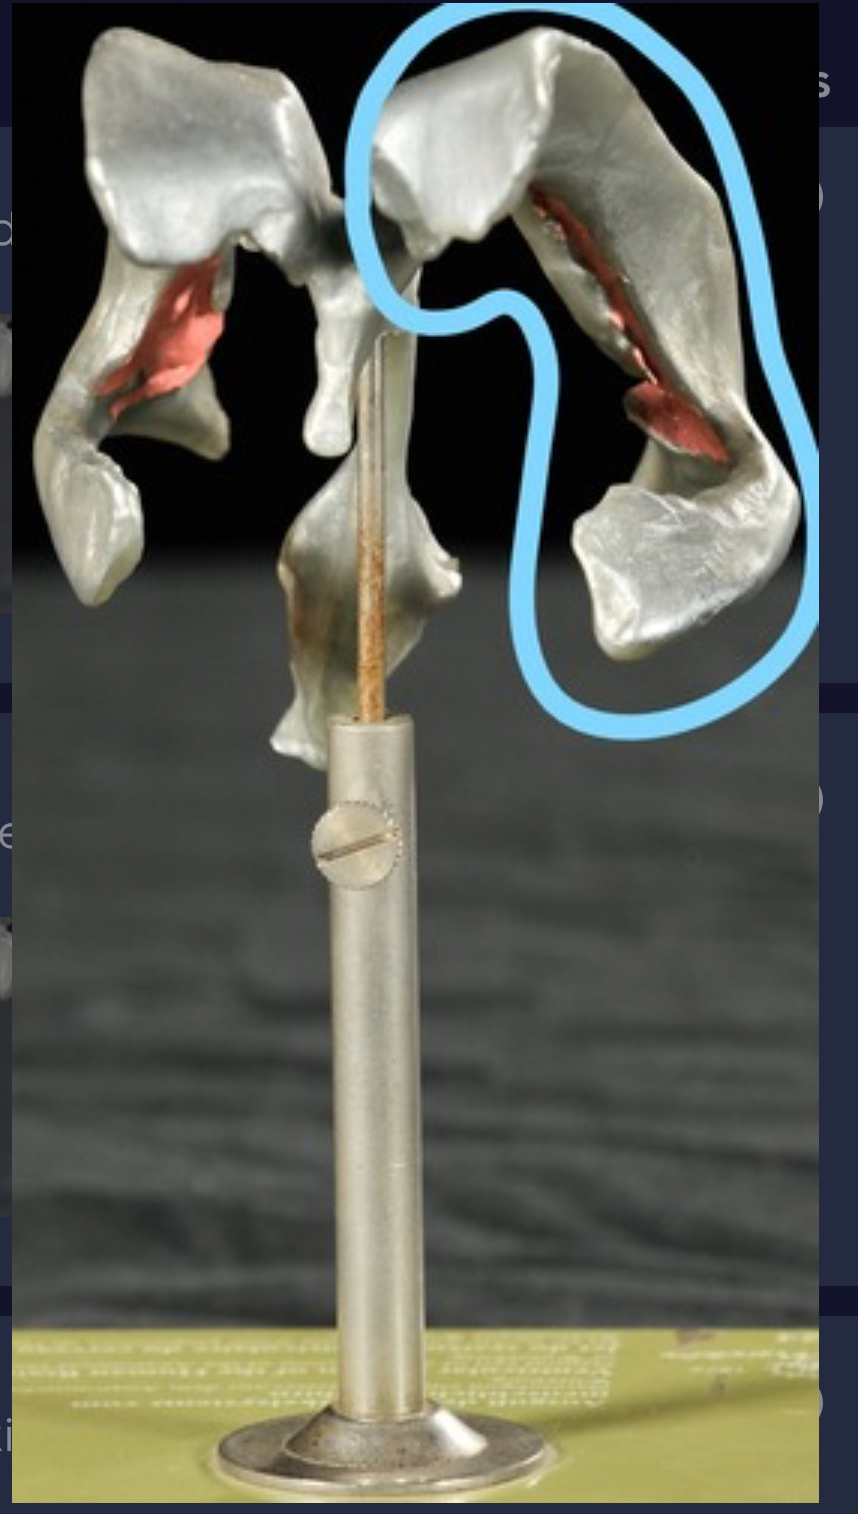

Left lateral ventricle

Right lateral ventricle

Anterior horn of ventricle

Posterior horn of ventricle

Inferior horn of ventricle

Third ventricle

Cerebral aqueduct

Fourth ventricle of stick model